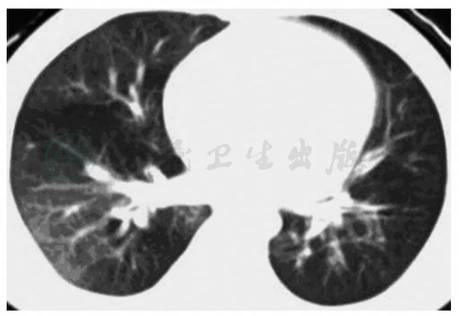

(三)CT检查

患侧胸廓狭小,表现为胸廓轻度塌陷,肋间隙略窄,纵隔气管轻度偏向患侧。患侧肺透亮度增高,中内带非血管性纹理增强、紊乱,外带纹理稀少,界限分明。患侧肺血管纹理细小、稀少。可有支气管扩张、“马赛克”征等表现(图2)。

图2单侧透明肺的CT表现